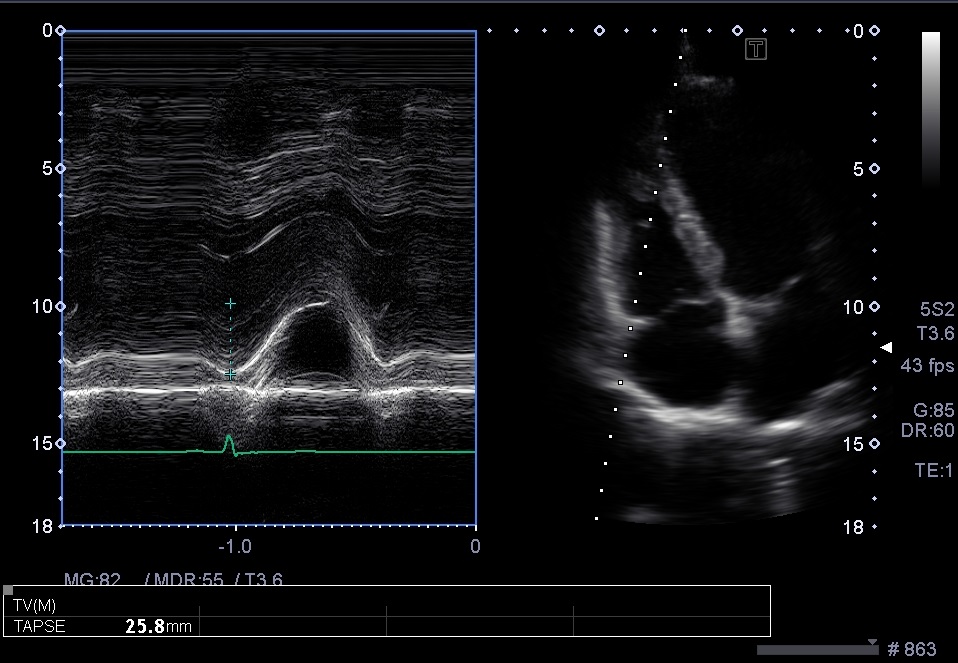

Measurement of tricuspid annular plane systolic excursion (TAPSE) TAPSE Echo Tapse Bedeutung Tapse ist eine akronym für tricuspid annular plane systolic excursion, einen messwert in der echokardiografie mit dem die. Although there are many emerging. Tapse steht für tricuspid annular plane systolic excursion. Das ist ein begriff aus der medizin, der in der herzdiagnostik verwendet wird. Tricuspid annular plane systolic excursion (tapse) can provide a point of care ultrasound assessment of right. Echo Tapse Bedeutung.